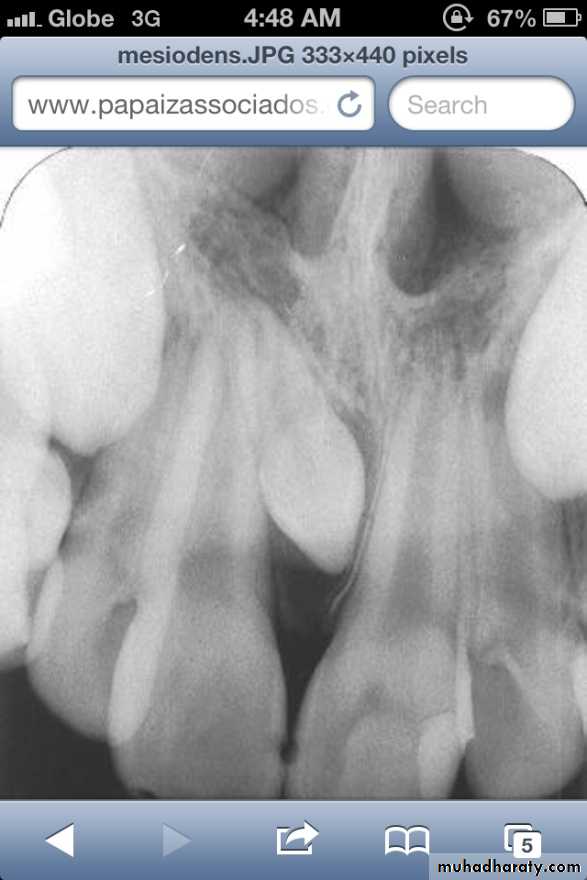

• Mesiodens :When they occur between the maxillary central incisors.

• Common region of the jaws to be affected is the premaxilla.

Many supernumerary teeth never erupt, but they may delay eruption of nearby teeth or cause other dental problems.

If they erupt, they can cause malalignment of the normal dentition.

They may cause root resorption or interfere with the normal eruption sequence.

Follicles of unerupted supernumerary teeth occasionally develop

into dentigerous cysts.